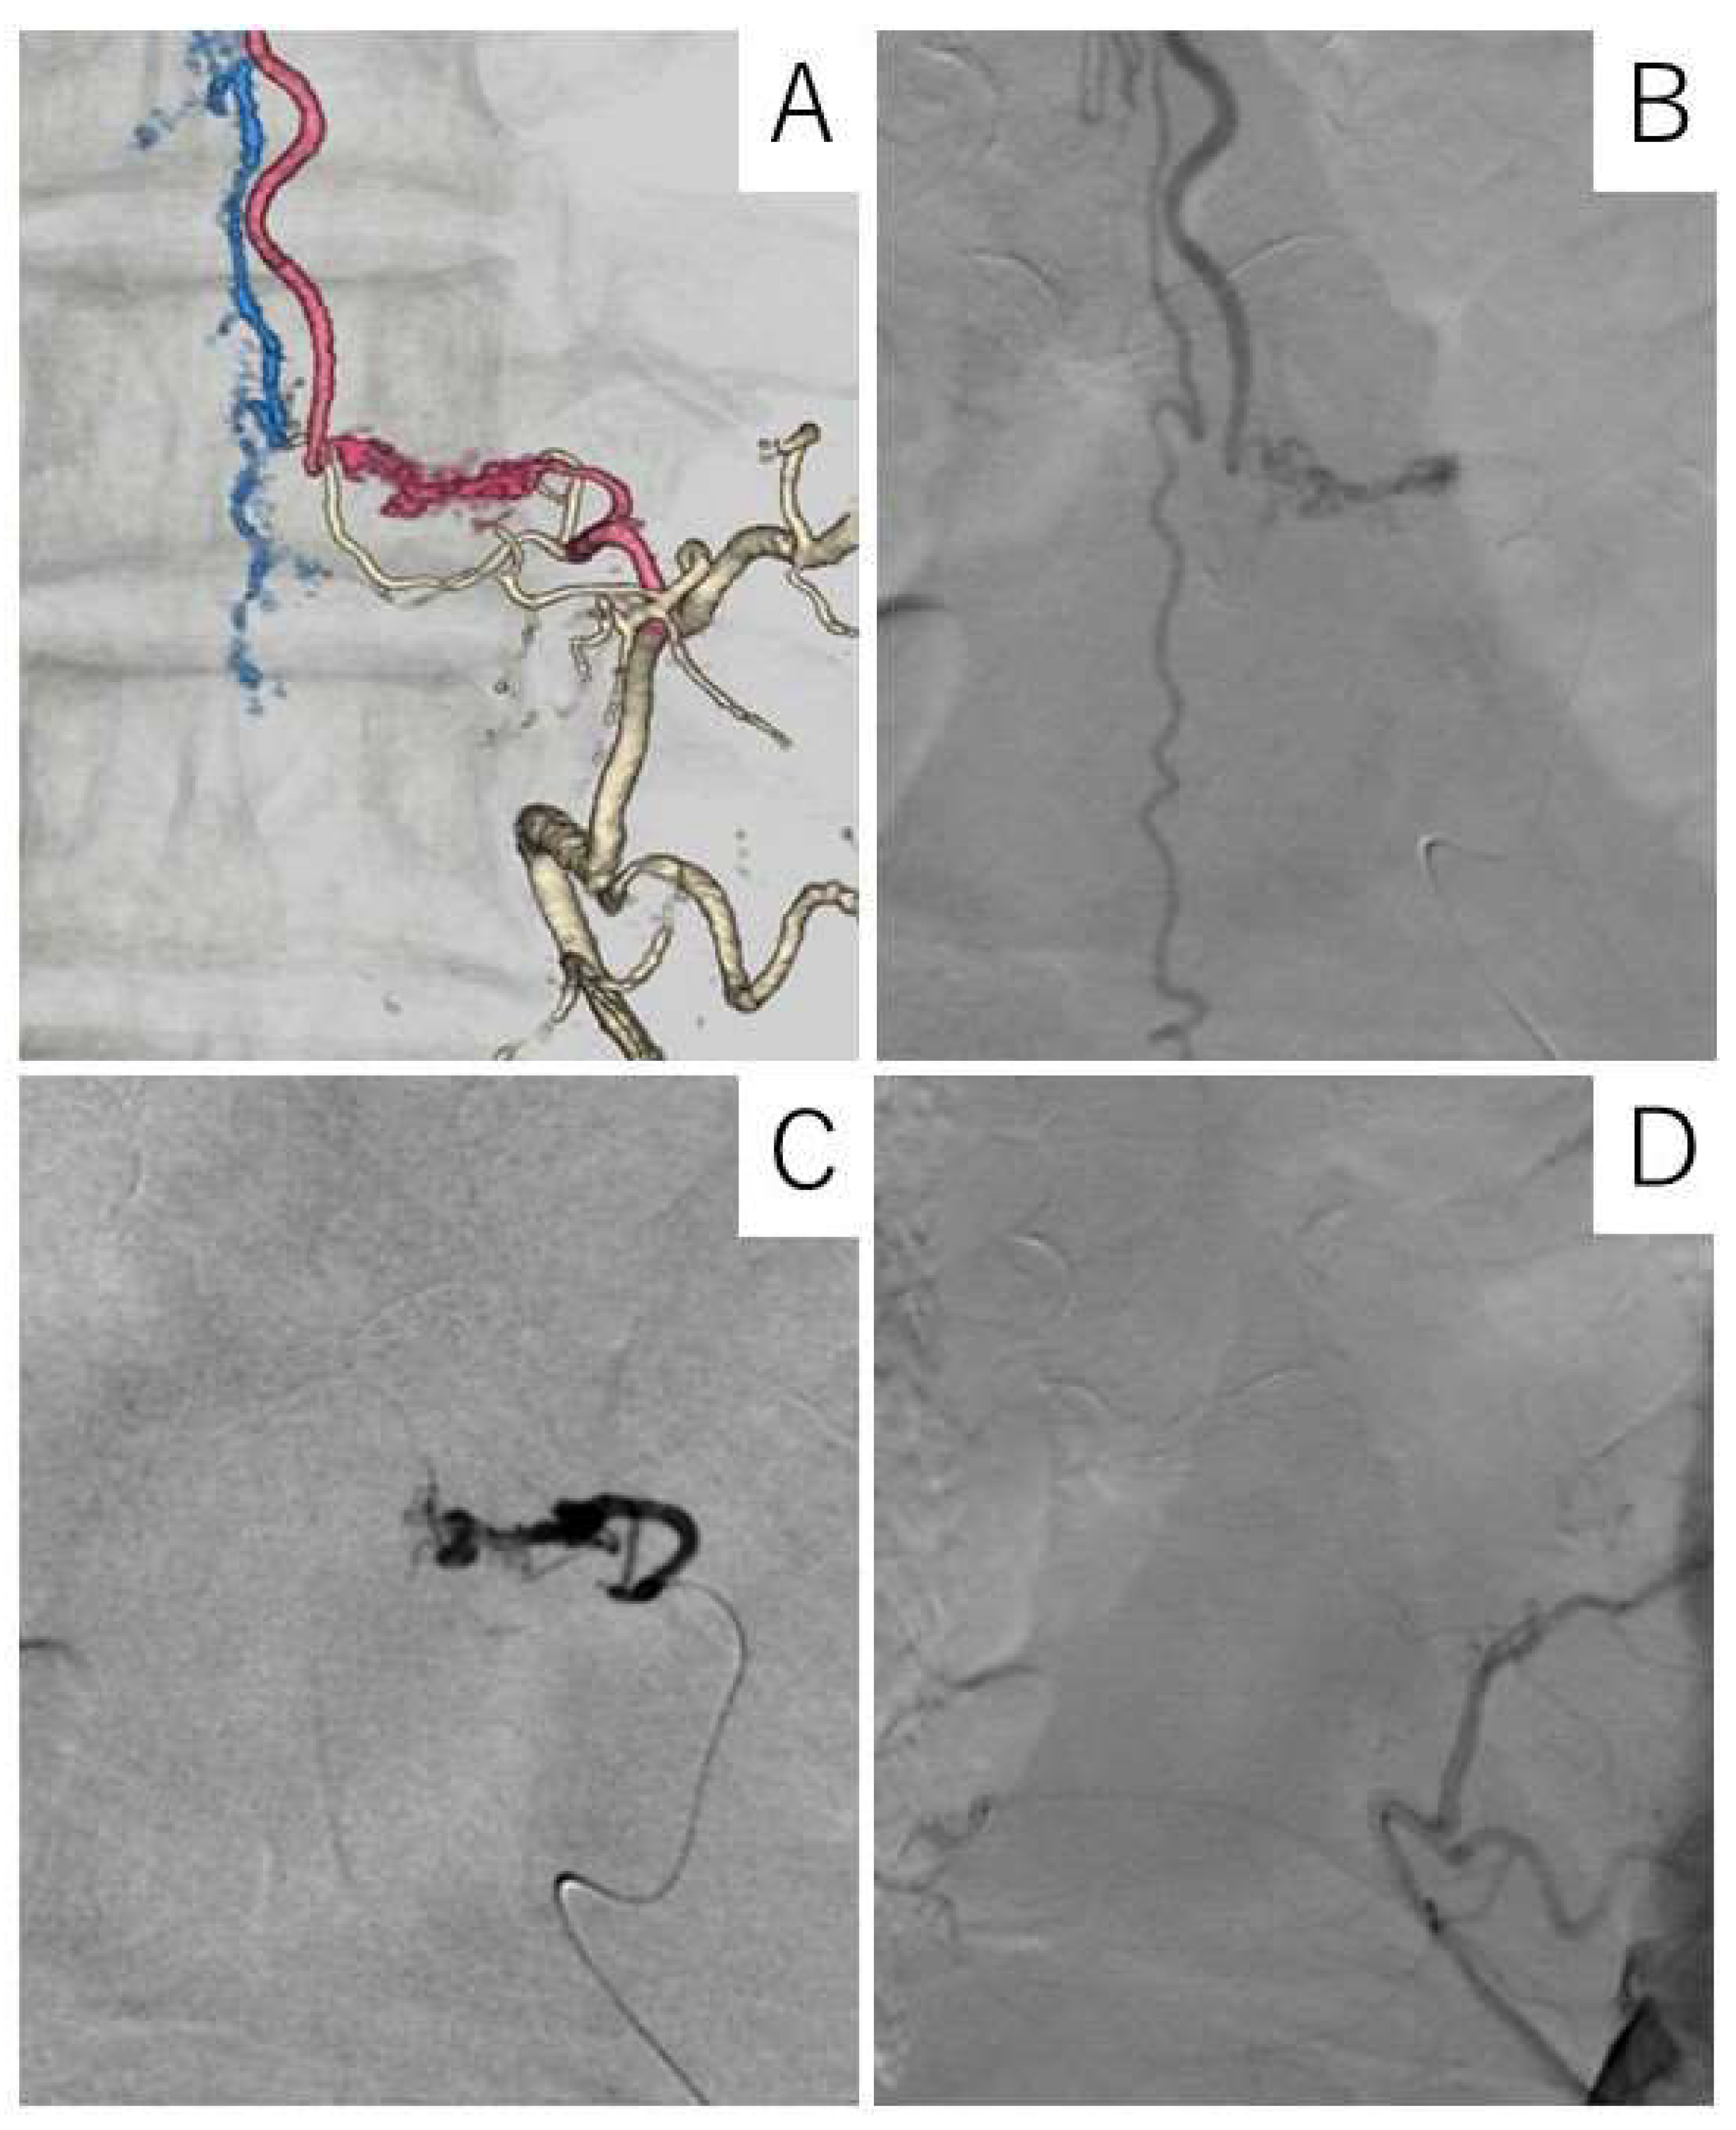

Case Description

4.4. Diagnostic Procedure

4.5. Treatment and Outcomes